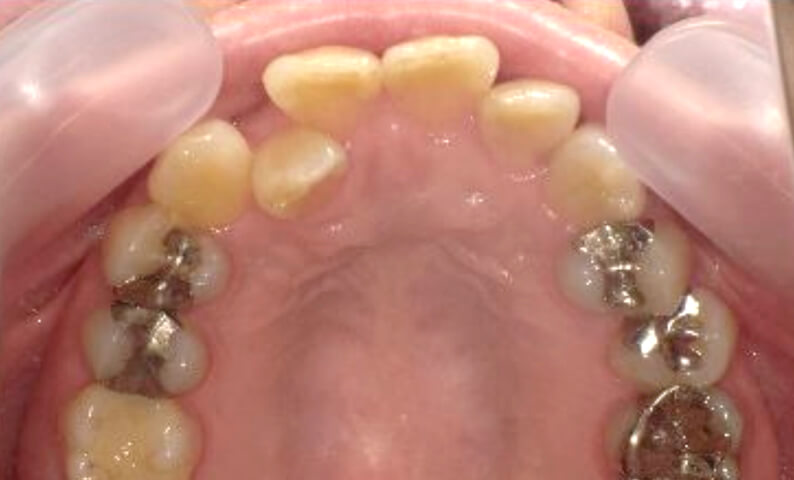

症例_002 下顎だけの部分矯正

治療期間:6ヶ月金額:21万円+税女性前歯のデコボコ下の前歯だけ

| Before | After |